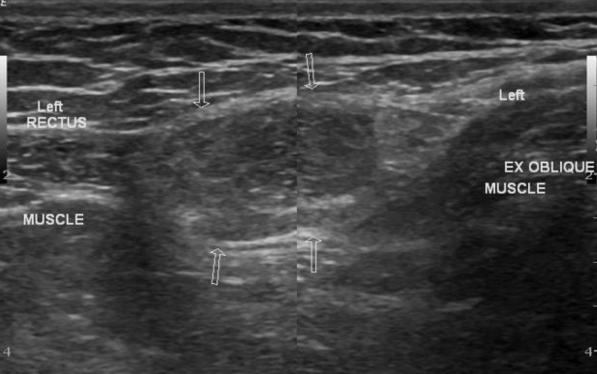

Hernie de Spiegel

- Suspect si

- Pas de peristaltisme

- Pas de changement au valsalva

- DD

- Contenu graisseux

- Masse du cordon spermatique

- Adenopathie